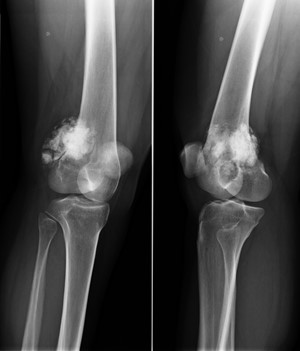

Также необходимо провести рентген, сканирование костной ткани, сделать биопсию кости, КТ.